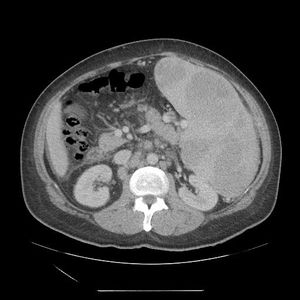

Massive enlargement of spleen.Rule out CML, chronic malaria, kala azar, etc.

All right cll patient